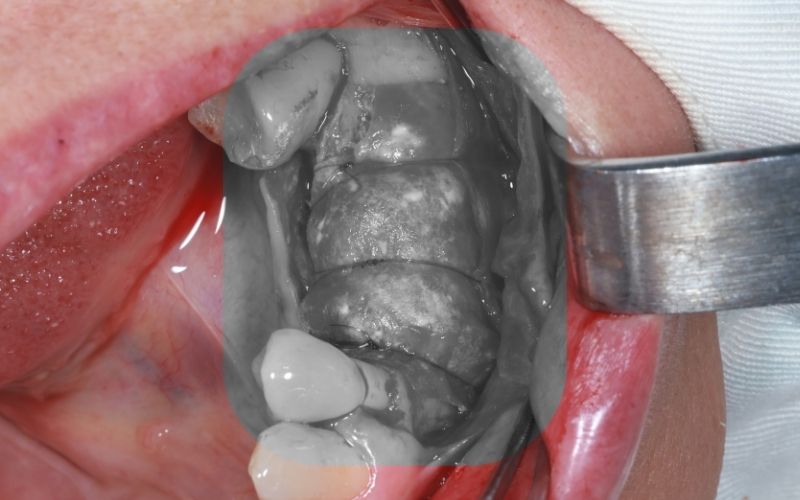

6.3. Tiến hành phẫu thuật ghép xương

Bác sĩ tạo vạt niêm mạc, xử lý bề mặt xương hàm, sau đó đặt vật liệu ghép xương và màng xương sinh học đúng vị trí cần phục hồi nhằm hỗ trợ tái tạo xương và tăng độ ổn định cho vùng ghép.